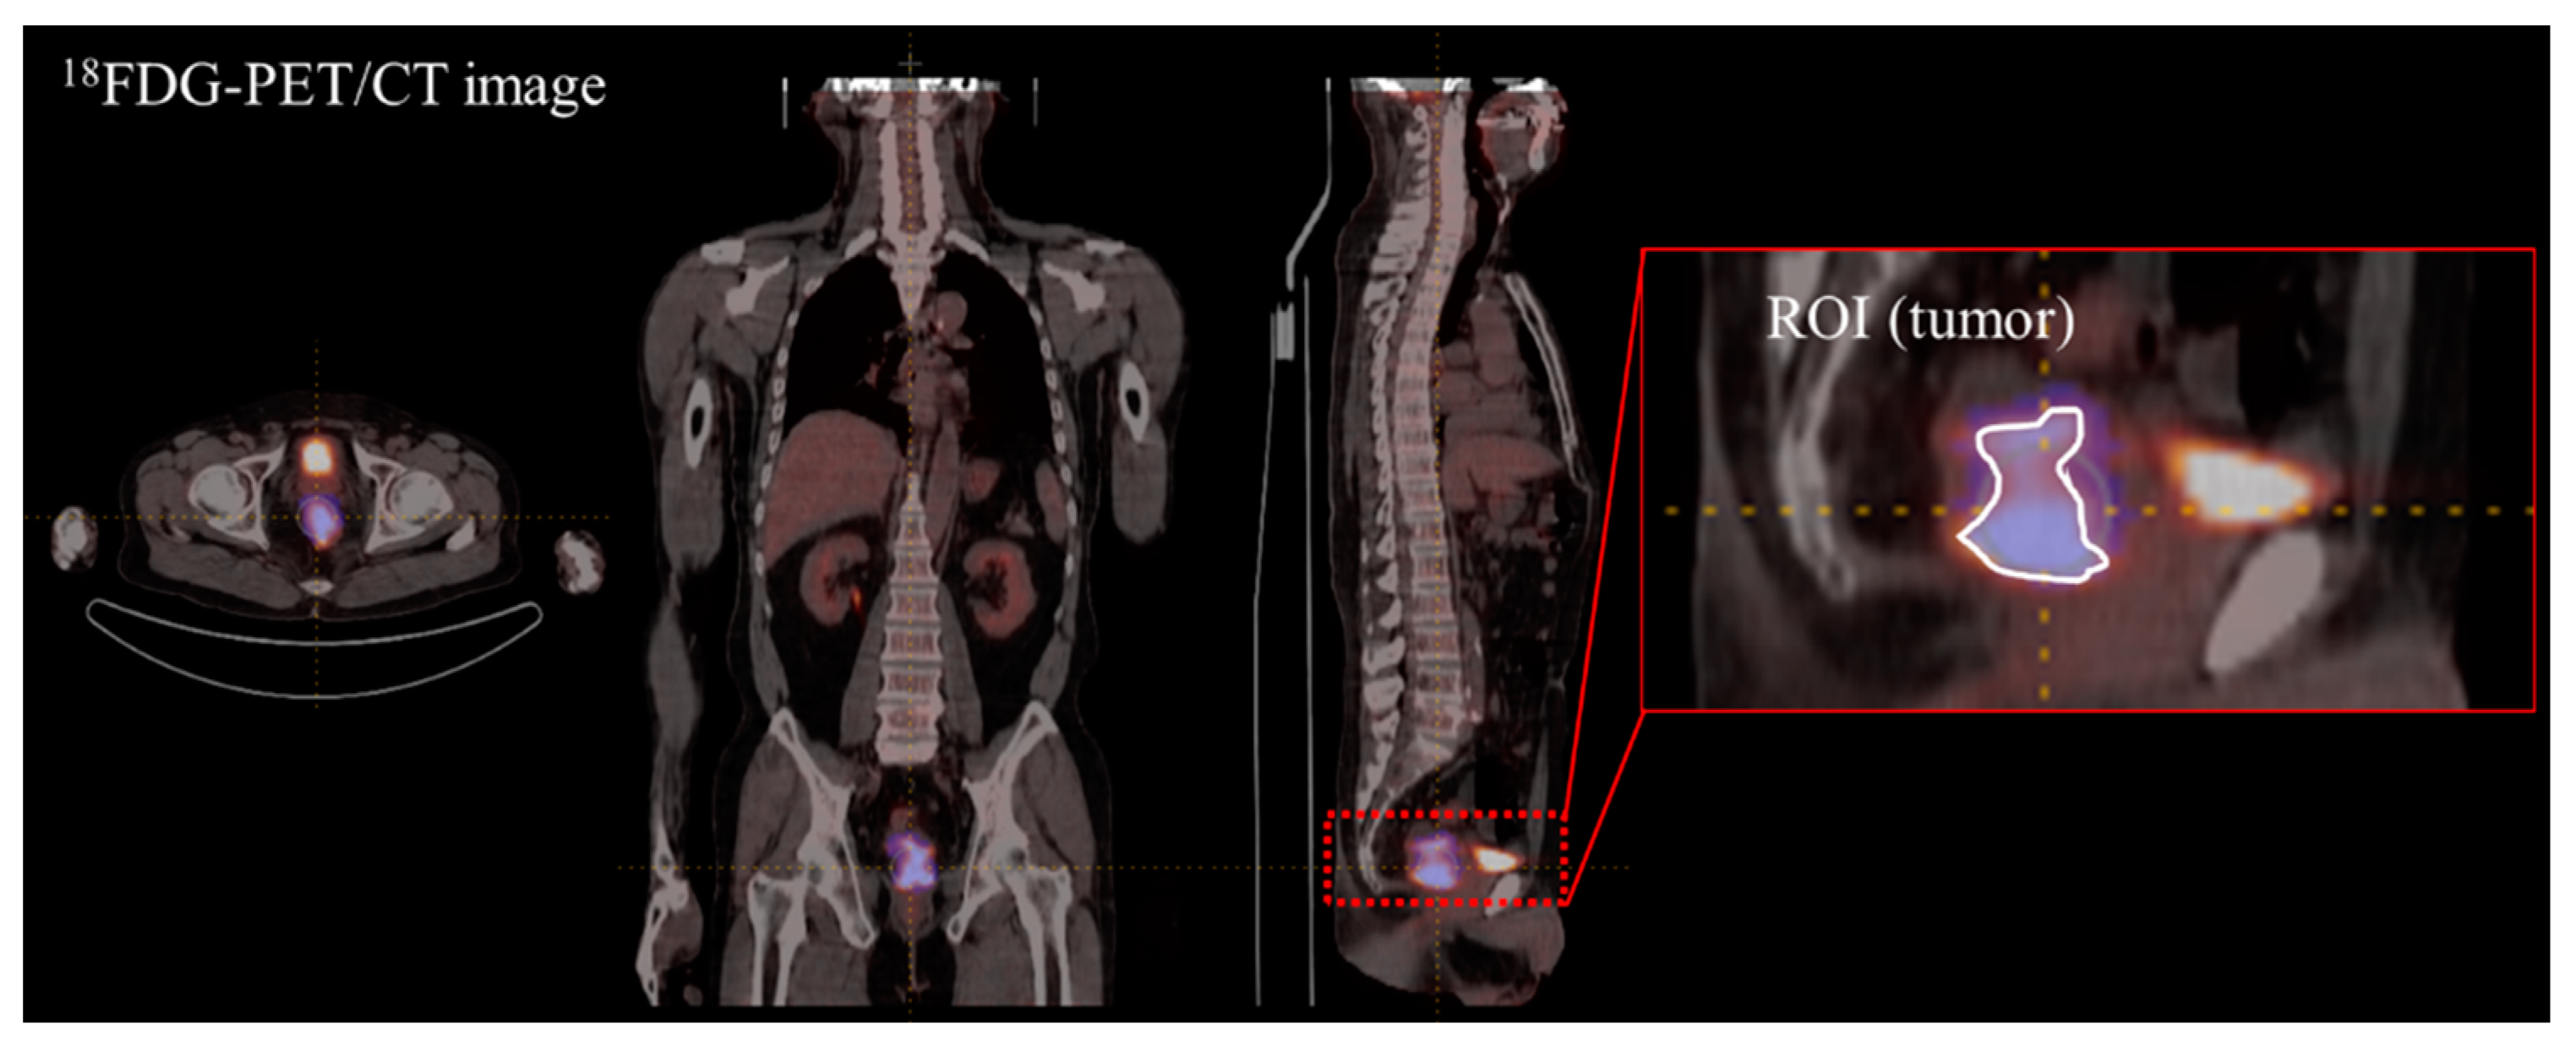

2.2. Image Feature Extraction